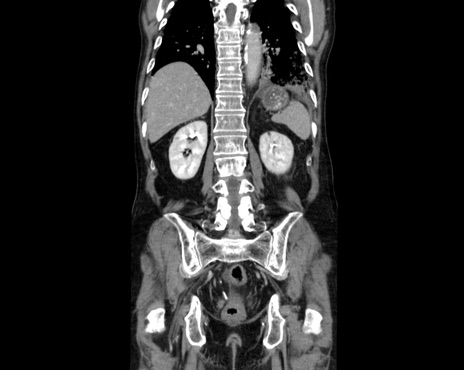

症例26(冠状断像)

【症例】80歳代男性

【主訴】嘔吐

【現病歴】昨晩2回嘔吐あり、今朝になっても嘔吐あり。来院。

【既往歴】胃潰瘍

【身体所見】意識清明、BT 37.6℃、BP 166/95mmHg、HR 100bpm、SpO2 97%、腹部:平坦・軟、腸蠕動音聴取良好、圧痛なし。

【データ】WBC 21900、CRP 1.4